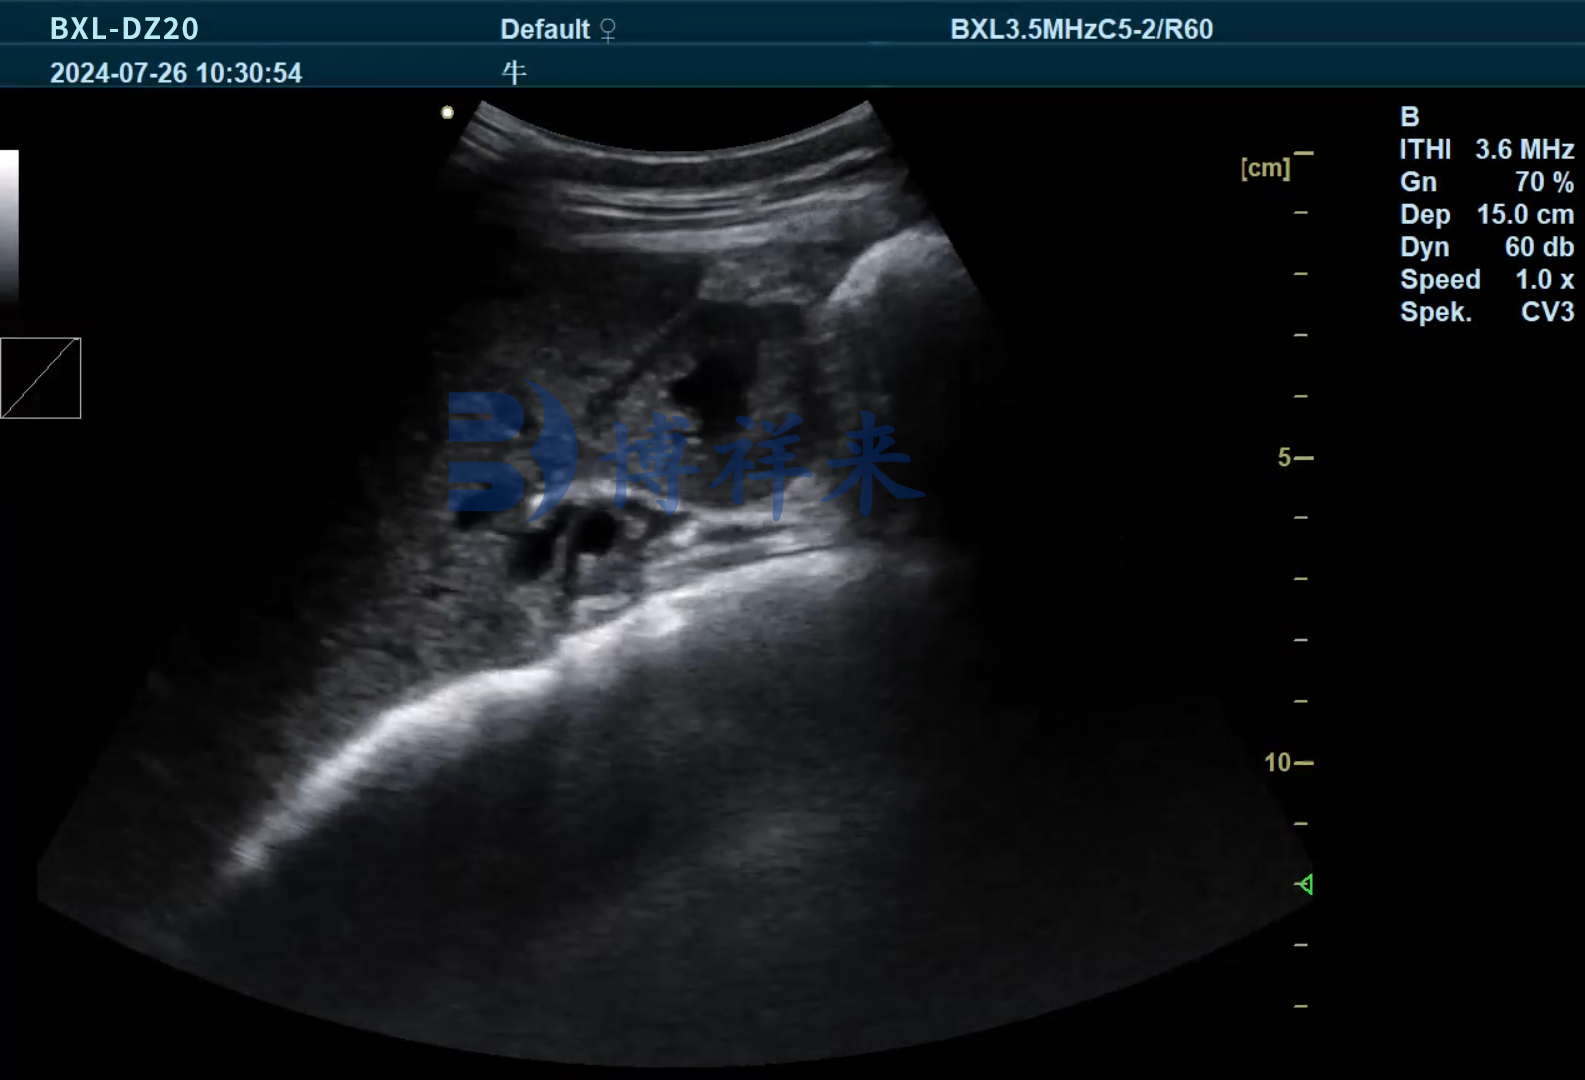

传统上,只有在屠宰时解剖胆囊才能“碰运气”发现牛黄。而现在,借助高分辨率的兽用B超机,可以对牛的肝胆区域进行实时影像观察,提前发现以下异常信号:

这些B超影像特征为判断牛黄存在提供了技术支持,尤其适用于高价值种牛、斗牛、或专门饲养牛黄的个体牛只的日常筛查与管理。

作为专业兽用B超设备制造商,博祥来推出的BXL-DZ20等型号,配备高清成像微凸探头,特别适用于肝胆区域的深层组织观察,可用于检测胆囊结石、肝脏病变、卵巢状态等,是养殖场全面掌握牛只健康和附加价值的理想工具。